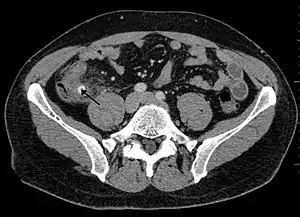

Appendicitis as seen on CT imaging

Diagnosis is based on a medical history (symptoms) and physical examination, which can be supported by an elevation of neutrophilic white blood cells and imaging studies if needed. Histories fall into two categories, typical and atypical.

A CT scan demonstrating acute appendicitis (note the appendix has a diameter of 17.1 mm and there is surrounding fat stranding)

A fecalith marked by the arrow that has resulted in acute appendicitis.

Where it is readily available, computed tomography (CT) has become frequently used, especially in people whose diagnosis is not obvious on history and physical examination. Although some concerns about interpretation are identified, a 2019 Cochrane review found that sensitivity and specificity of CT for the diagnosis of acute appendicitis in adults was high.[49] Concerns about radiation tend to limit use of CT in pregnant women and children, especially with the increasingly widespread usage of MRI.[50][51]

The accurate diagnosis of appendicitis is multi-tiered, with the size of the appendix having the strongest positive predictive value, while indirect features can either increase or decrease sensitivity and specificity. A size of over 6 mm is both 95% sensitive and specific for appendicitis.[52]

However, because the appendix can be filled with fecal material, causing intraluminal distention, this criterion has shown limited utility in more recent meta-analyses.[53] This is as opposed to ultrasound, in which the wall of the appendix can be more easily distinguished from intraluminal feces. In such scenarios, ancillary features such as increased wall enhancement as compared to adjacent bowel and inflammation of the surrounding fat, or fat stranding, can be supportive of the diagnosis. However, their absence does not preclude it. In severe cases with perforation, an adjacent phlegmon or abscess can be seen. Dense fluid layering in the pelvis can also result, related to either pus or enteric spillage. When patients are thin or younger, the relative absence of fat can make the appendix and surrounding fat stranding difficult to see.[53]